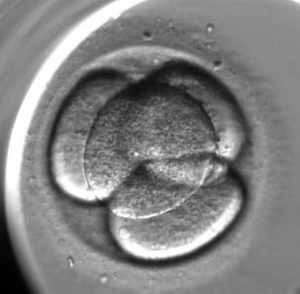

L’enregistrement du développement de l’embryon est le suivant :

Pour l’évaluation de la qualité des embryons on utilise la méthode d’analyse morphologique. Les embryons sont évalués selon les critères suivants : la quantité des blastomères, l’égalité des blastomères et la présence de fragmentation (des blastomères normaux qui ont été détruits). Cependant, cette méthode qui est la plus ancienne a ses inconvénients, elle est subjective (elle dépend de l’expérience et du niveau de l’embryologiste), un embryon est extrêmement variable durant son développement un embryon de mauvaise qualité de deux jours peut se transformer en un bel enfant en bonne santé. En ce moment, on utilise une nouvelle méthode d’évaluation de la qualité des embryons c’est l’embryoscopie. Son principe est le suivant : toutes les 10 ou 20 minutes on prend une photo de l’embryon en 7 couches, avec l’utilisation d’un programme informatique, on applique les images l’une sur l’autre pour en faire une video, c’est « le résumé » de chaque embryon. Avec l’utilisation d’un programme informatique spécifique, on mesure les paramètres clés du développement embryonnaire :